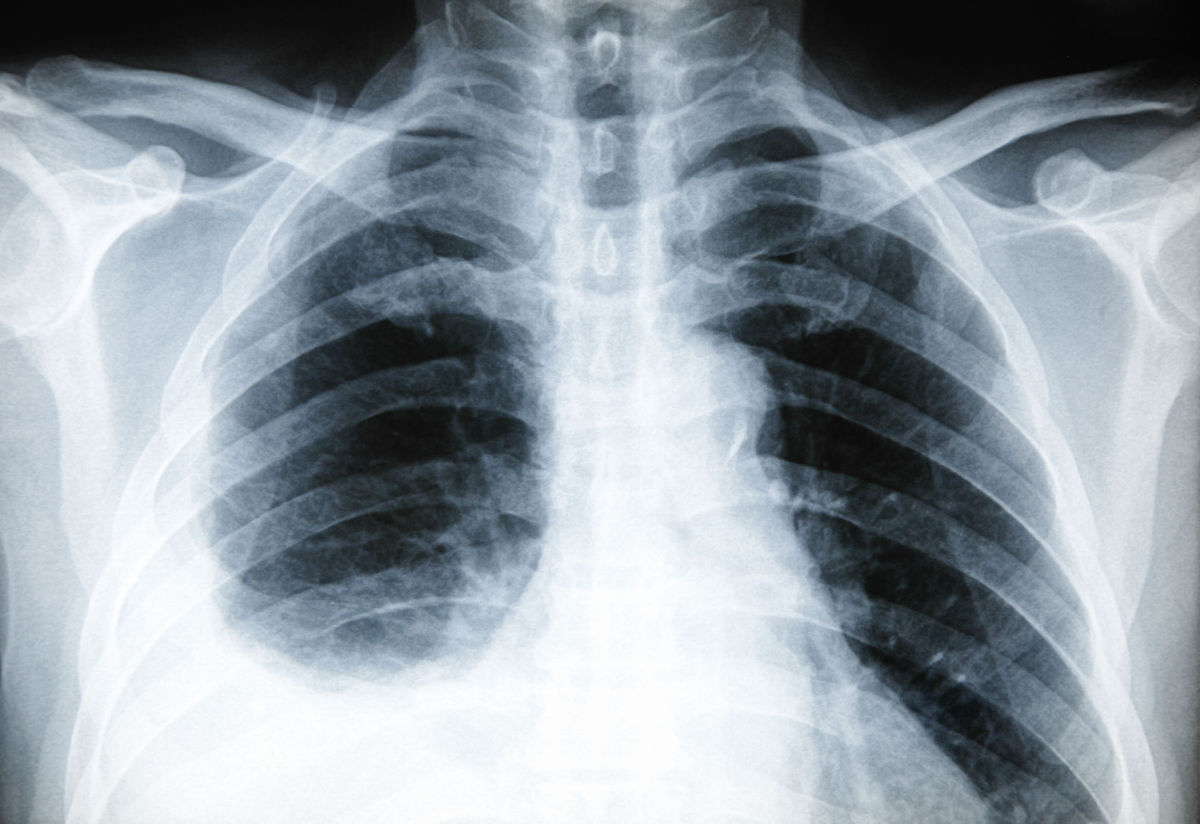

What you never knew about Pleurisy

pleurisy